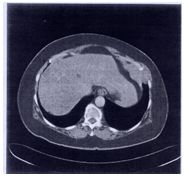

85. 58歲女性,因胸痛求診,經檢查後,發現為一胸壁腫瘤 (Chest Wall Tumor) (如圖)。 關於胸壁腫瘤之敘述,以下何者最為正確? (A) 大部分之胸壁腫瘤為良性腫瘤 (B) 大多數之惡性胸壁腫瘤為原發性惡性腫瘤 (C) 大多數之惡性胸壁腫瘤會有疼痛之症狀 (D) 最常見之良性胸壁腫瘤為Fibrous Dysplasia